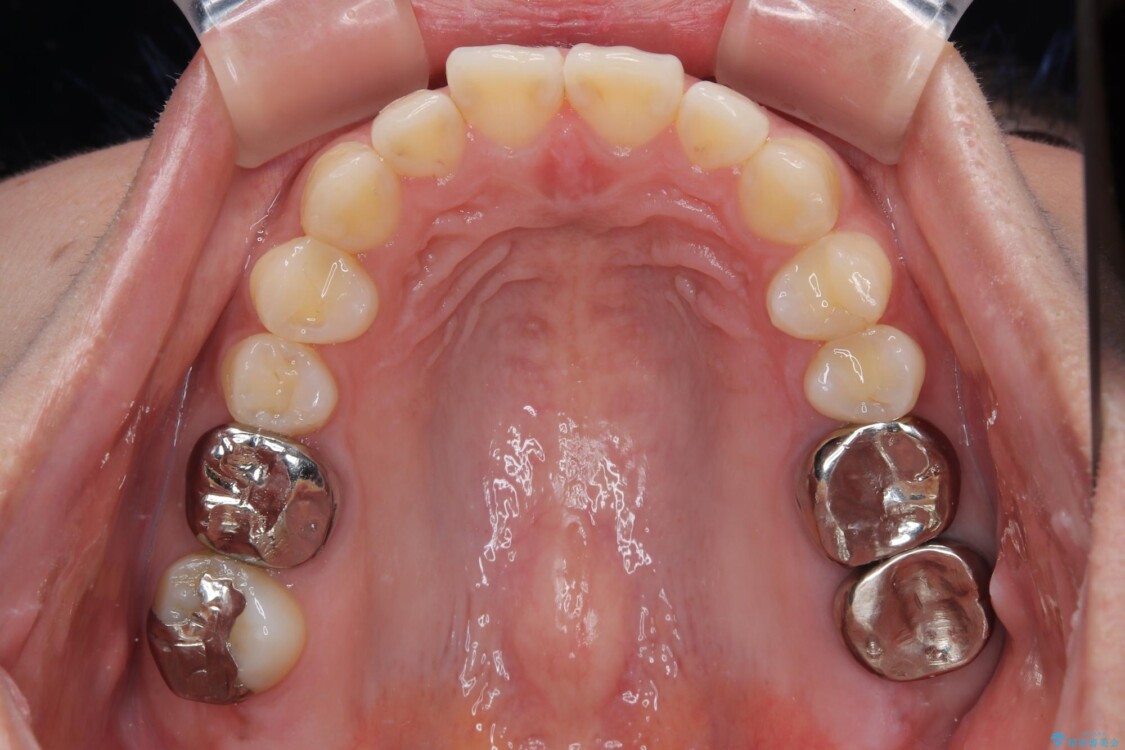

「1年前に抜歯した右下の奥歯にインプラントを入れたい」とのことで来院されました。

インプラント希望部位は右下第一大臼歯と第二大臼歯です。

しかし、噛み合わせの相手である右上の第二大臼歯が、長期間噛み合う歯がなかった影響で**挺出(歯が下に伸びてくる状態)してしまっており、このままではインプラントを埋入して被せもの(上部構造)を入れるためのスペースが不足している状態でした。

治療前

• 挺出歯を圧下してスペースを確保!目立たない部分矯正で下顎大臼歯にインプラント治療を実現 治療前画像